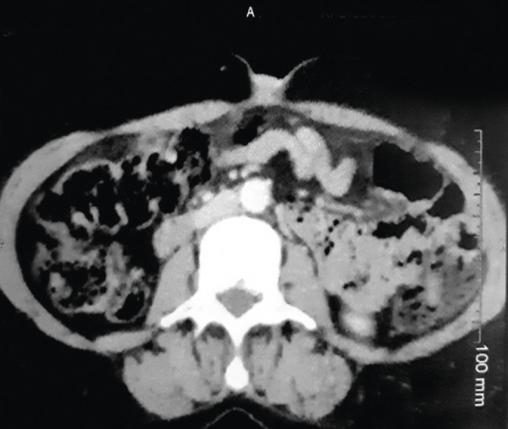

Cette femme de 54 ans consultait pour un nodule ombilical associé à des douleurs de l’hypochondre gauche, et une anorexie depuis 4 mois. À l’examen, cette tuméfaction ombilicale était douloureuse et ferme (fig. 1 ). La tomodensitométrie thoraco-abdomino-pelvienne (fig. 2 et 3 ) montrait un processus tumoral du corps du pancréas avec infiltration de la graisse périlésionnelle, métastases hépatiques et carcinose péritonéale. L’imagerie par résonance magnétique notait un processus tumoral nécrotique du corps du pancréas avec métastases hépatiques et nodules péritonéaux carcinomateux. La biopsie cutanée du nodule montrait une lymphangite carcinomateuse dermique avec des cellules tumorales carcinomateuses en petits amas dans les lymphatiques et un foyer d’infiltration épidermique pagétoïde, concluant à une lymphangite carcinomateuse dermique. Ce nodule dit de Sœur Marie-Josèphe révélait un adénocarcinome pancréatique. La patiente décédait 3 mois plus tard.